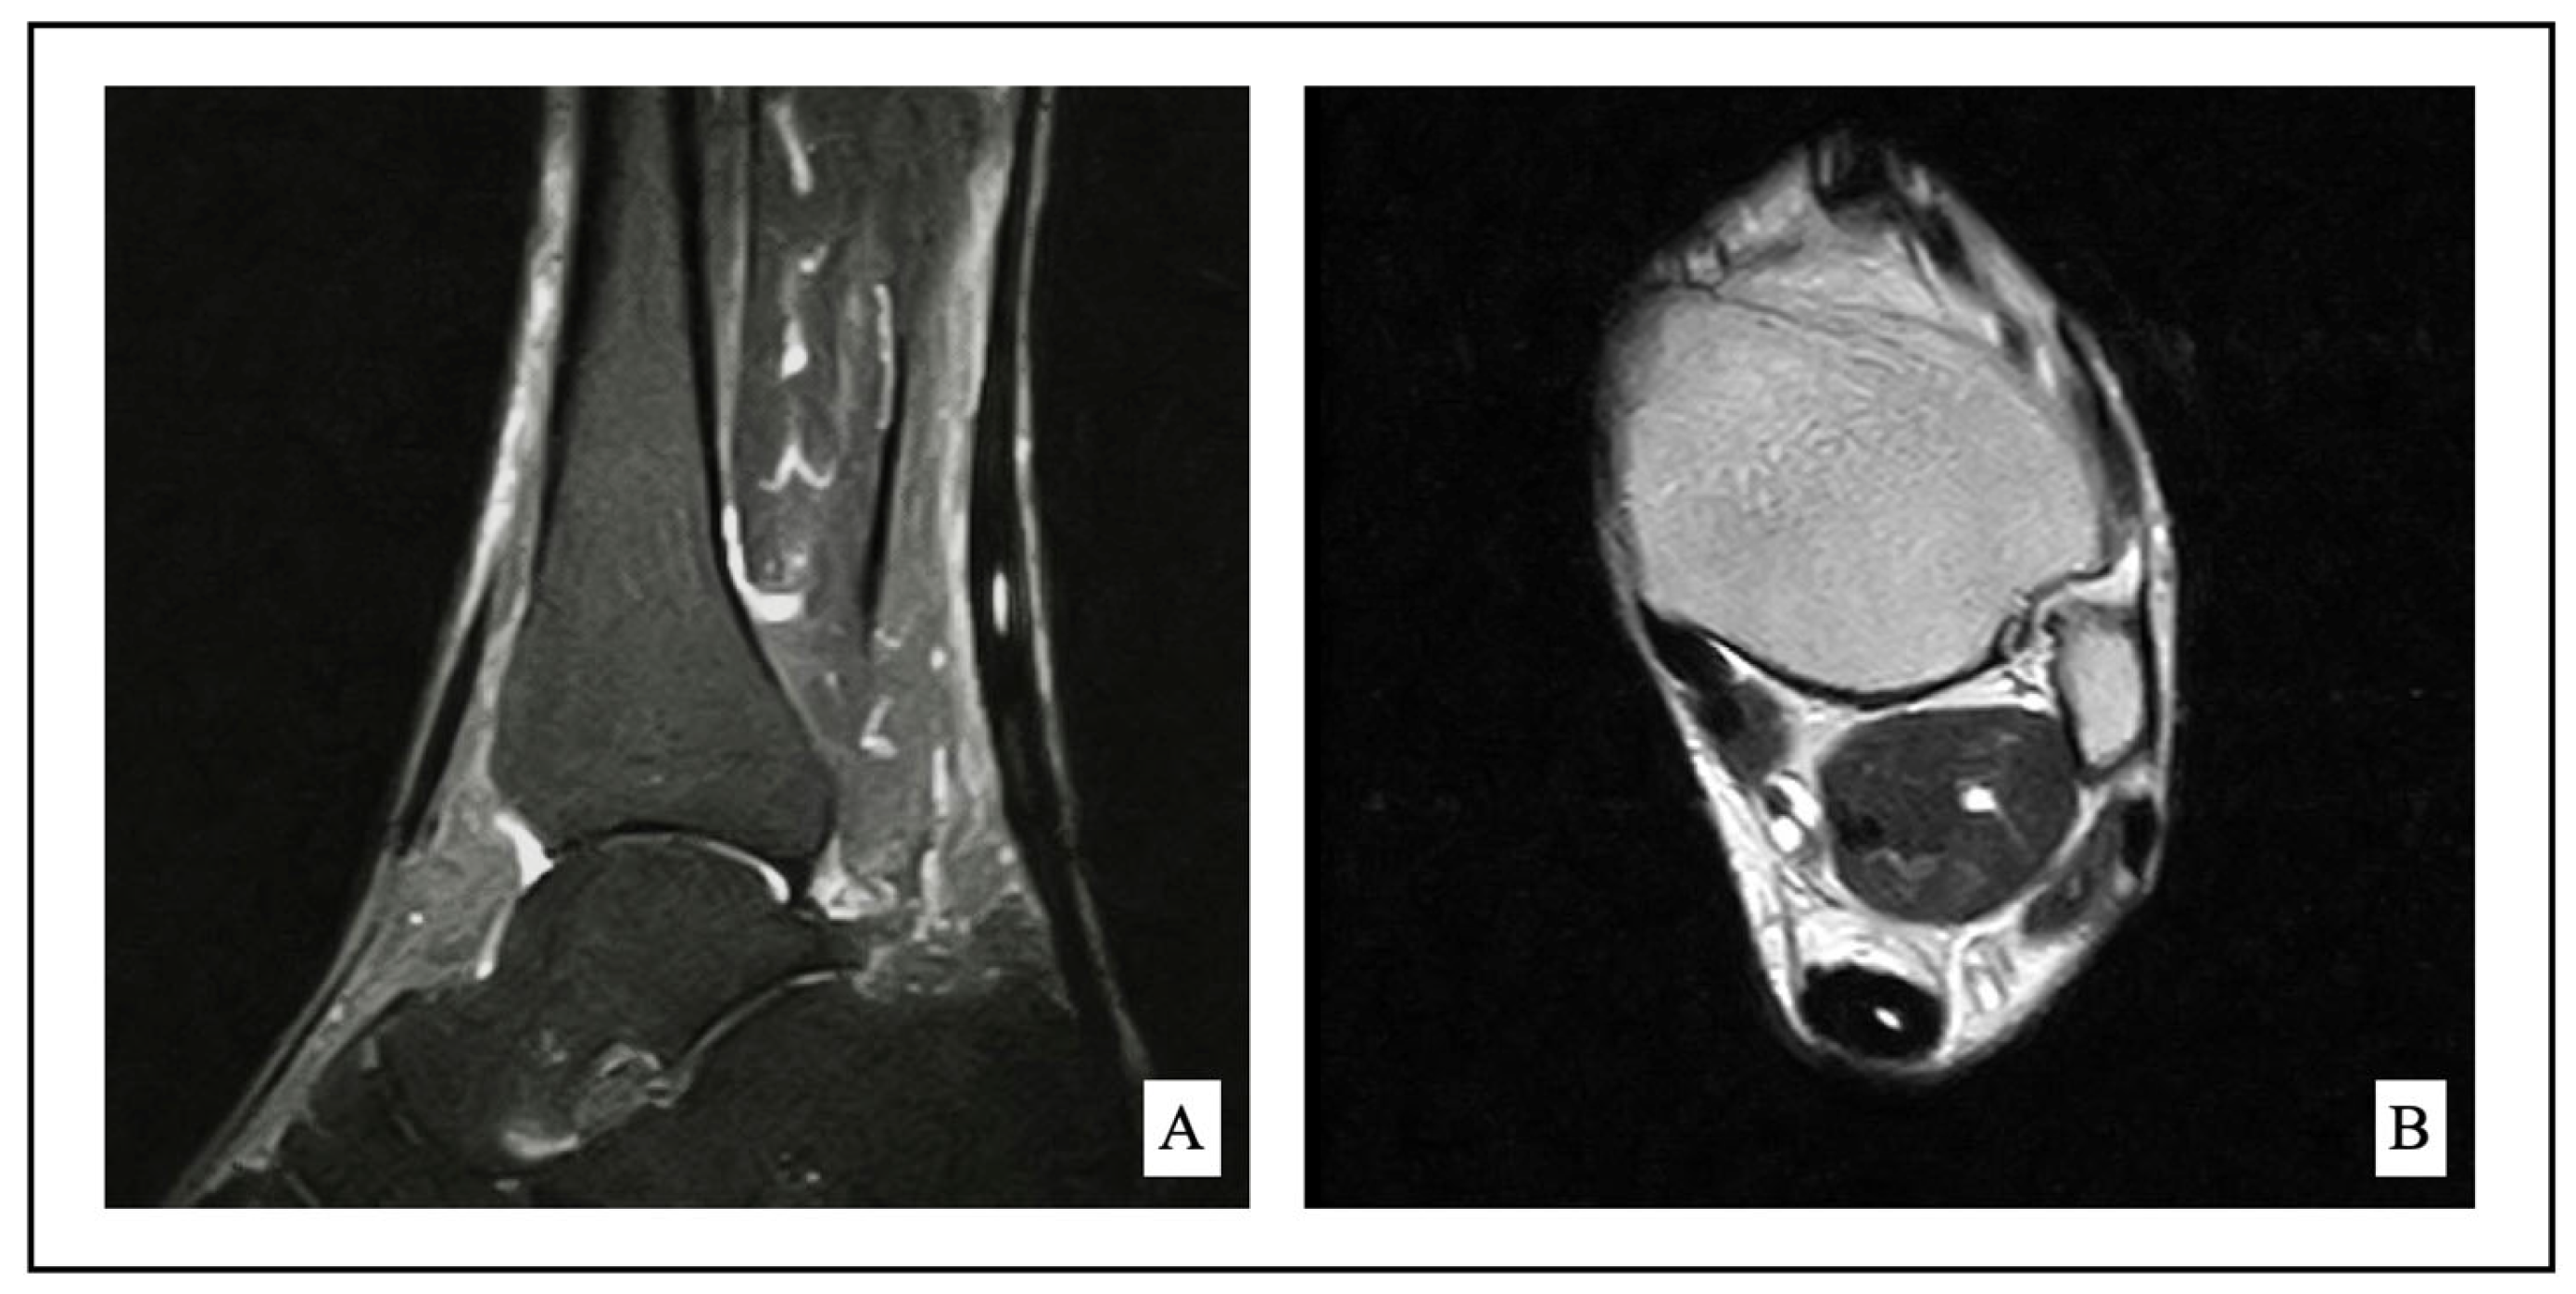

2.4. Surgical Technique